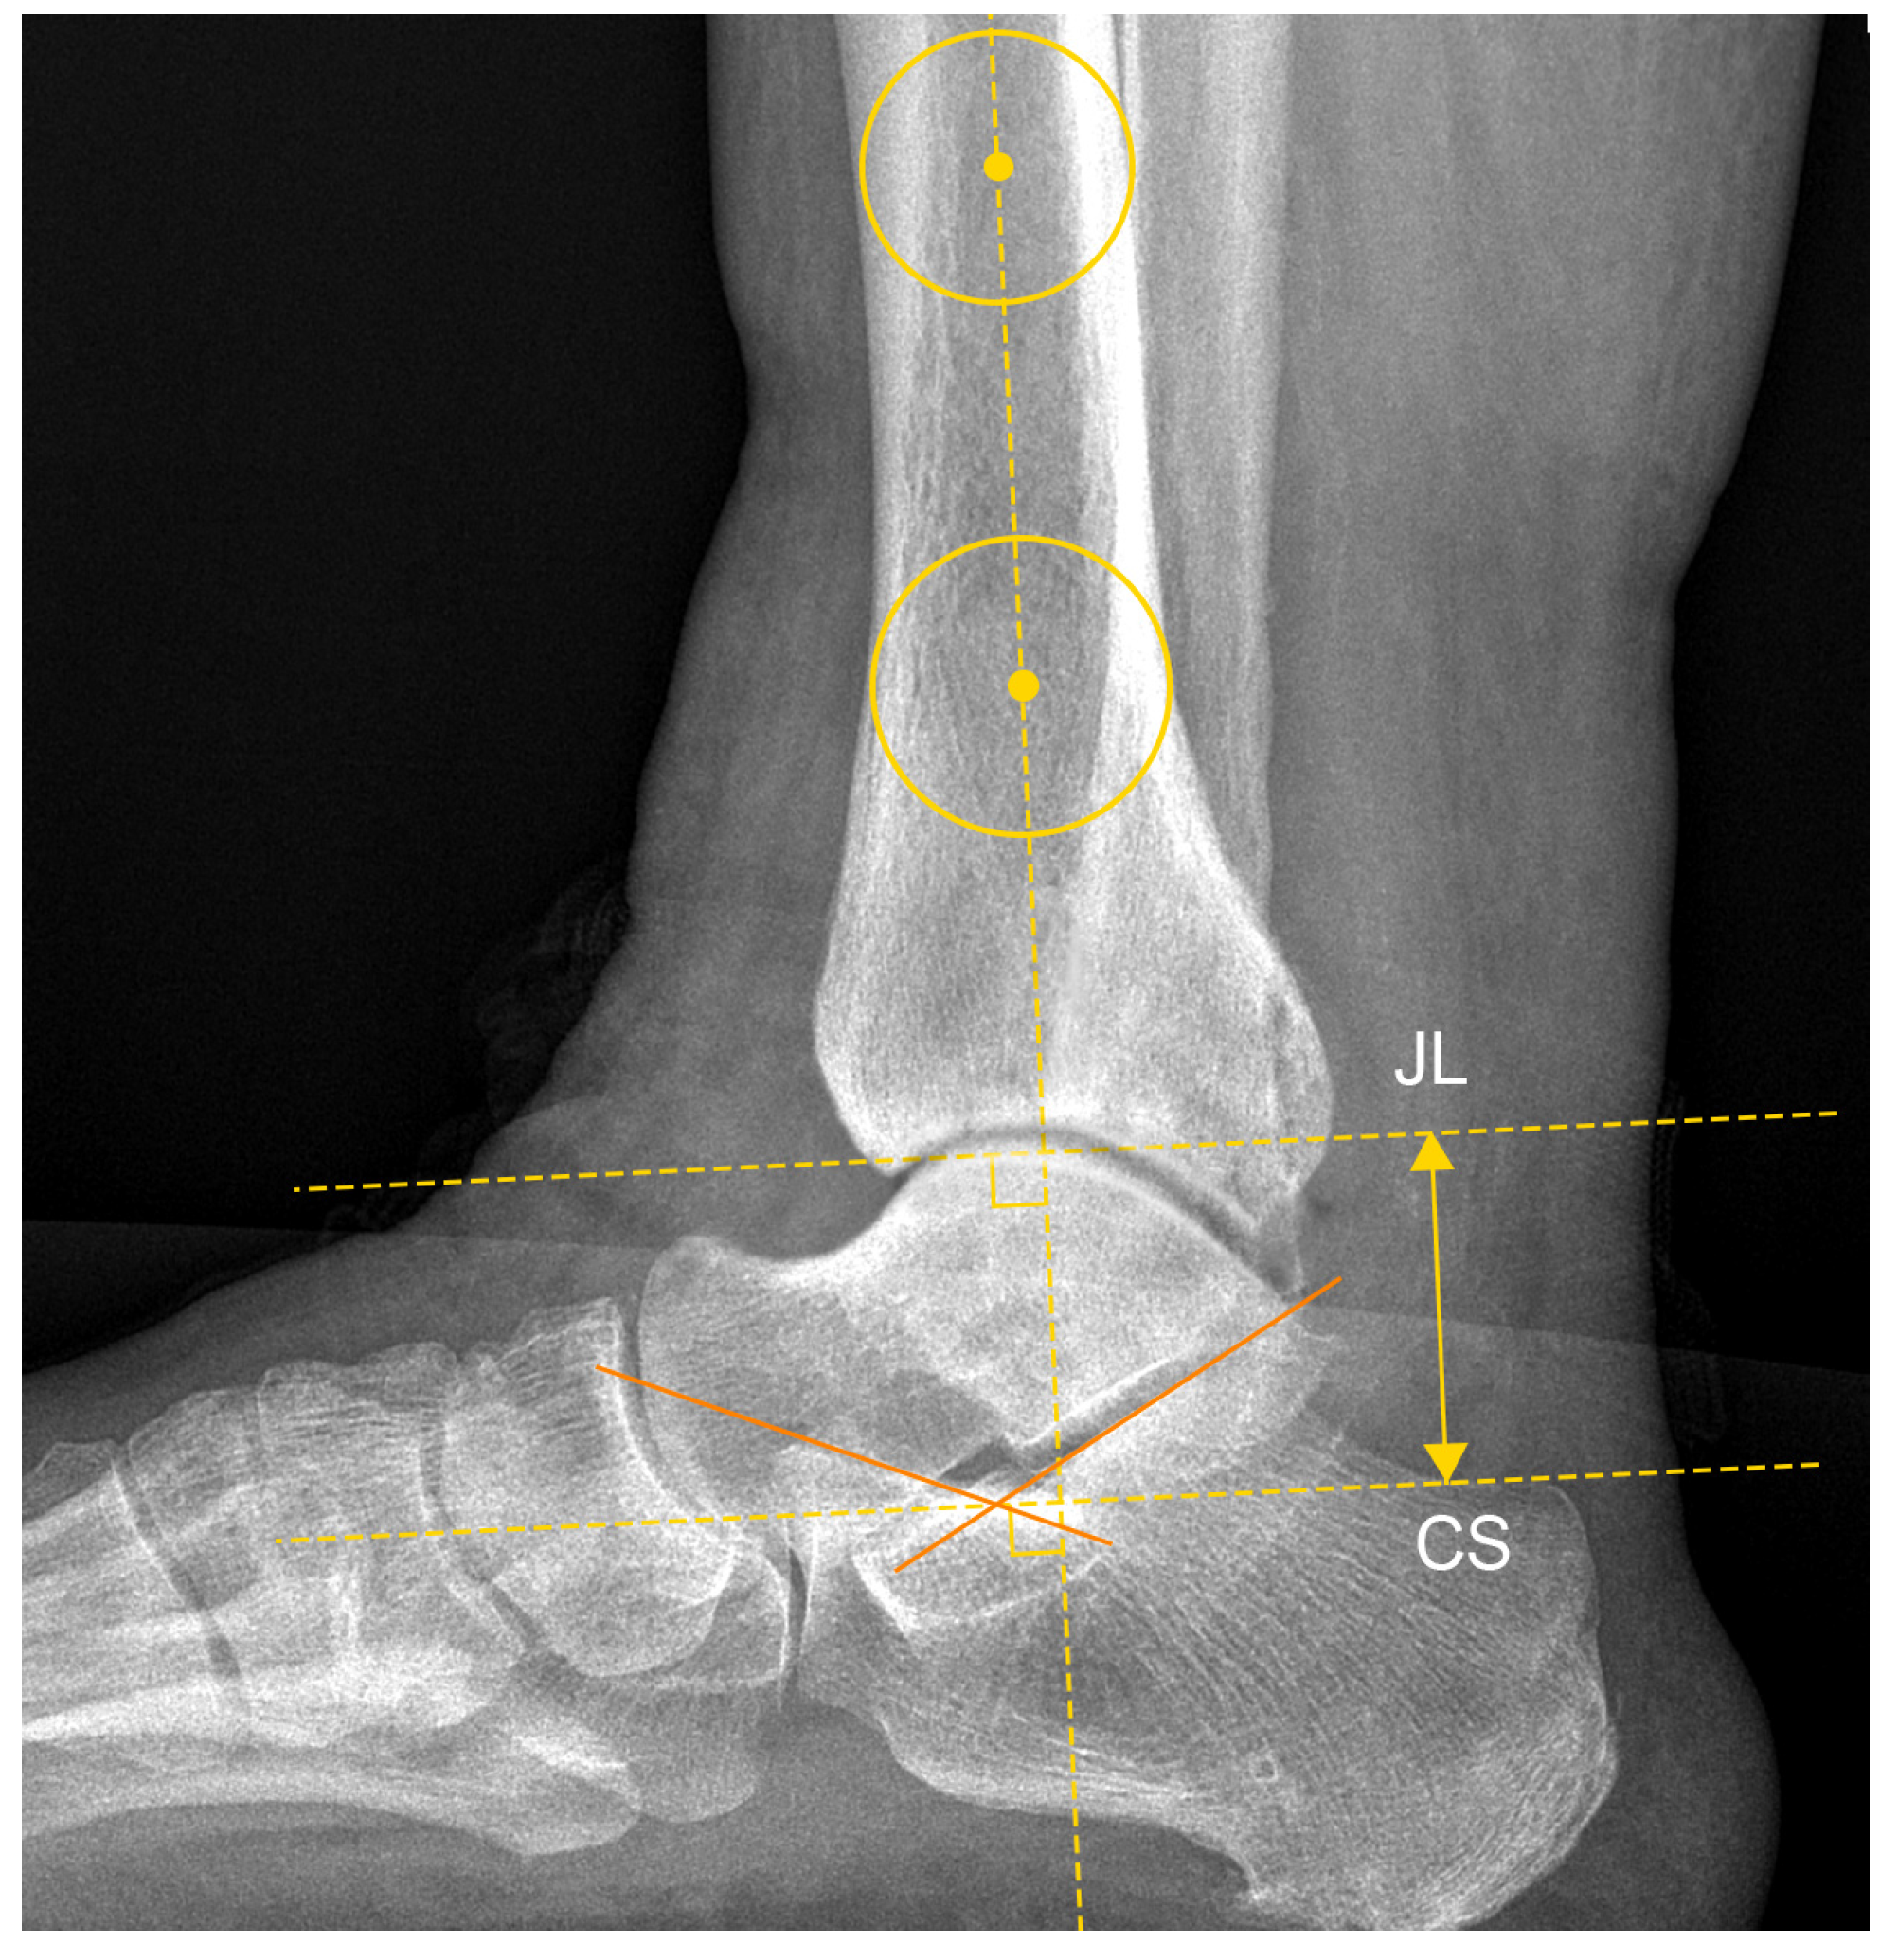

| JLHR 1 | 2.23 ± 0.54 | 1.94 | 1.64–3.44 | 24.3% |

| LM-JL 2 distance | 2.30 ± 0.39 cm | 2.12 cm | 1.78–3.19 cm | 17.0% |

| MM-JL 3 distance | 1.21 ± 0.30 cm | 1.11 cm | 0.89–1.78 cm | 24.9% |

| CS-JL 4 distance | 3.82 ± 0.51 cm | 3.87 cm | 2.94–4.53 cm | 13.4% |

| JLHR 1 (contralateral) | 1.95 ± 0.54 | 1.92 | 1.49–3.54 | 27.7% |

| LM-JL 2 distance (contralateral) | 2.21 ± 0.26 cm | 2.12 cm | 1.84–2.81 cm | 11.8% |

| MM-JL 3 distance (contralateral) | 1.00 ± 0.20 cm | 0.92 cm | 0.76–1.42 cm | 20.3% |

| CS-JL 4 distance (contralateral) | 4.04 ± 0.32 cm | 4.06 cm | 3.46–4.53 cm | 7.8% |